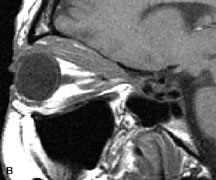

Tl relaxation time is the time required for the energized nuclei to give up the excess energy that was acquired from the RF pulse (high-energy state) and re-establish equilibrium (low-energy state) with the main magnetic field. The excess energy is released by these excited nuclei to the surrounding molecular environment, or lattice, and results in T1 relaxation, also called spin-lattice relaxation time. In different biologic tissues, hydrogen has a Tl ranging from a few hundred milliseconds to a couple of seconds. This range exists because local tissue factors affect the ability of specific protons to give up energy to the surrounding tissues. For example, hydrogen atoms attached to the carbon atoms of fat molecules relax much more rapidly than those attached to the oxygen atoms of water molecules. Viscosity, concentration, temperature, and molecular environment of the hydrogen atoms in the tissues also affect the T1 relaxation time. On a T1-weighted orbital image, fat, which has a very short T1 relaxation time, yields a high-intensity signal; the rectus muscles, which have an intermediate T1, yield an intermediate-intensity signal; and the vitreous, which has a long T1, yields a low-intensity signal (Fig. 8).5,8,16